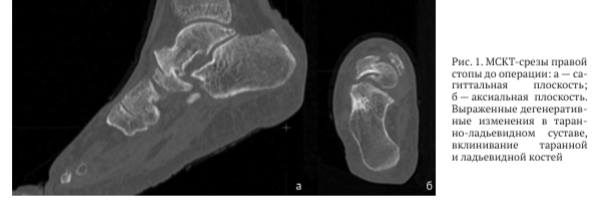

По данным компьютерной томографии выявлены грубая деформация и дислокация суставных поверхностей таранно-ладьевидного сустава, фрагментация ладьевидной кости, сцепленное вклинивание головки таранной кости и фрагмента ладьевидной кости (рис. 1)

-2